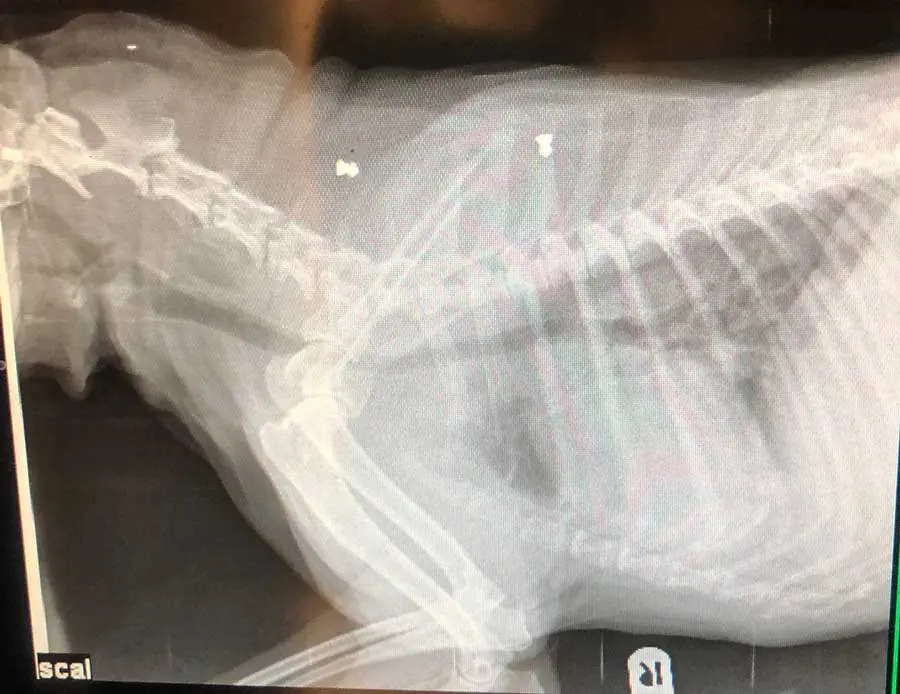

Radiographs can identify injuries or disease processes within the body by visualising bones, organs and other soft tissue structures – anything from fractures and osteosarcomas to bladder stones, foreign bodies and gastric dilation volvulus.

In the past 10 years, CT has become more readily available, with an increase in first opinion practices acquiring them. Similar to radiography, CT uses ionising x-ray radiation, but instead of creating a 2D image, CT spins in a helical motion with several detectors to create a 3D image that can show individual structures in the body in detail, without any overlap (Sieraj, 2025).